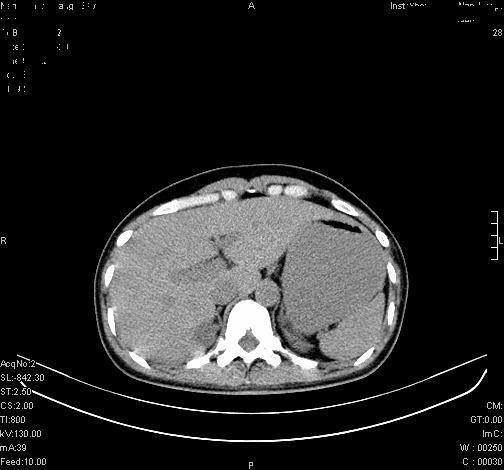

标题: CL0340:【】肾上腺囊肿,比较典型。

患者为年轻女性,查体发现右侧肾上腺囊性占位。无临床体征。

这么漂亮的图像,一看一目了然。典型的右侧肾上腺囊肿,周围有钙化。感谢搂主!

“肾上腺囊肿组织学分为4类:1)内皮细胞性,2)假性囊肿,3)寄生虫性,4)上皮细胞性。其中内皮细胞性最为常见。假性囊肿多为肾上腺内出血后遗留囊腔,囊壁无上皮细胞。寄生虫性多为包虫病引起。上皮性则很少见。”

这么明显的弧形钙化,多考虑包虫病所致的寄生虫性囊肿。

右侧肾上腺囊性密度灶囊壁有钙化。考虑肾上腺囊肿,结核?

右侧肾上腺囊肿,周围有钙化。